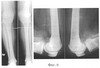

Фиг.4 – рентгеноконтрастные артрограммы правого коленного сустава пациентки до лечения;

На рентгенограммах коленных суставов: варусное отклонение голеней 10° во фронтальной плоскости. Суставная щель в медиальном отделе сужена, а в латеральном расширена (Фиг.3). На рентгеноконтрастных артрограммах коленных суставов в подколенных областях визуализируются кисты Бейкера (Фиг.4).